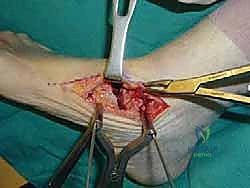

3. تصحيح التشوه (Deformity Correction)

بمجرد تحرير المفاصل، يقوم الدكتور هطيف بإعادة ترتيب العظام يدوياً لإصلاح التشوه. إذا كانت القدم مسطحة، يتم رفع القوس. وإذا كانت مقوسة للداخل، يتم تعديلها لتصبح مستقيمة. الهدف هو الحصول على قدم مستوية تماماً (Plantigrade Foot) توزع وزن الجسم بالتساوي.

4. الترقيع العظمي (Bone Grafting - إن لزم الأمر)

في بعض الحالات التي يوجد فيها فجوات عظمية أو قصر في العظام، يتم استخدام طعوم عظمية (تؤخذ غالباً من عظم الحوض للمريض أو من بنك العظام) لملء الفراغات وتحفيز التئام العظام (Osteogenesis).